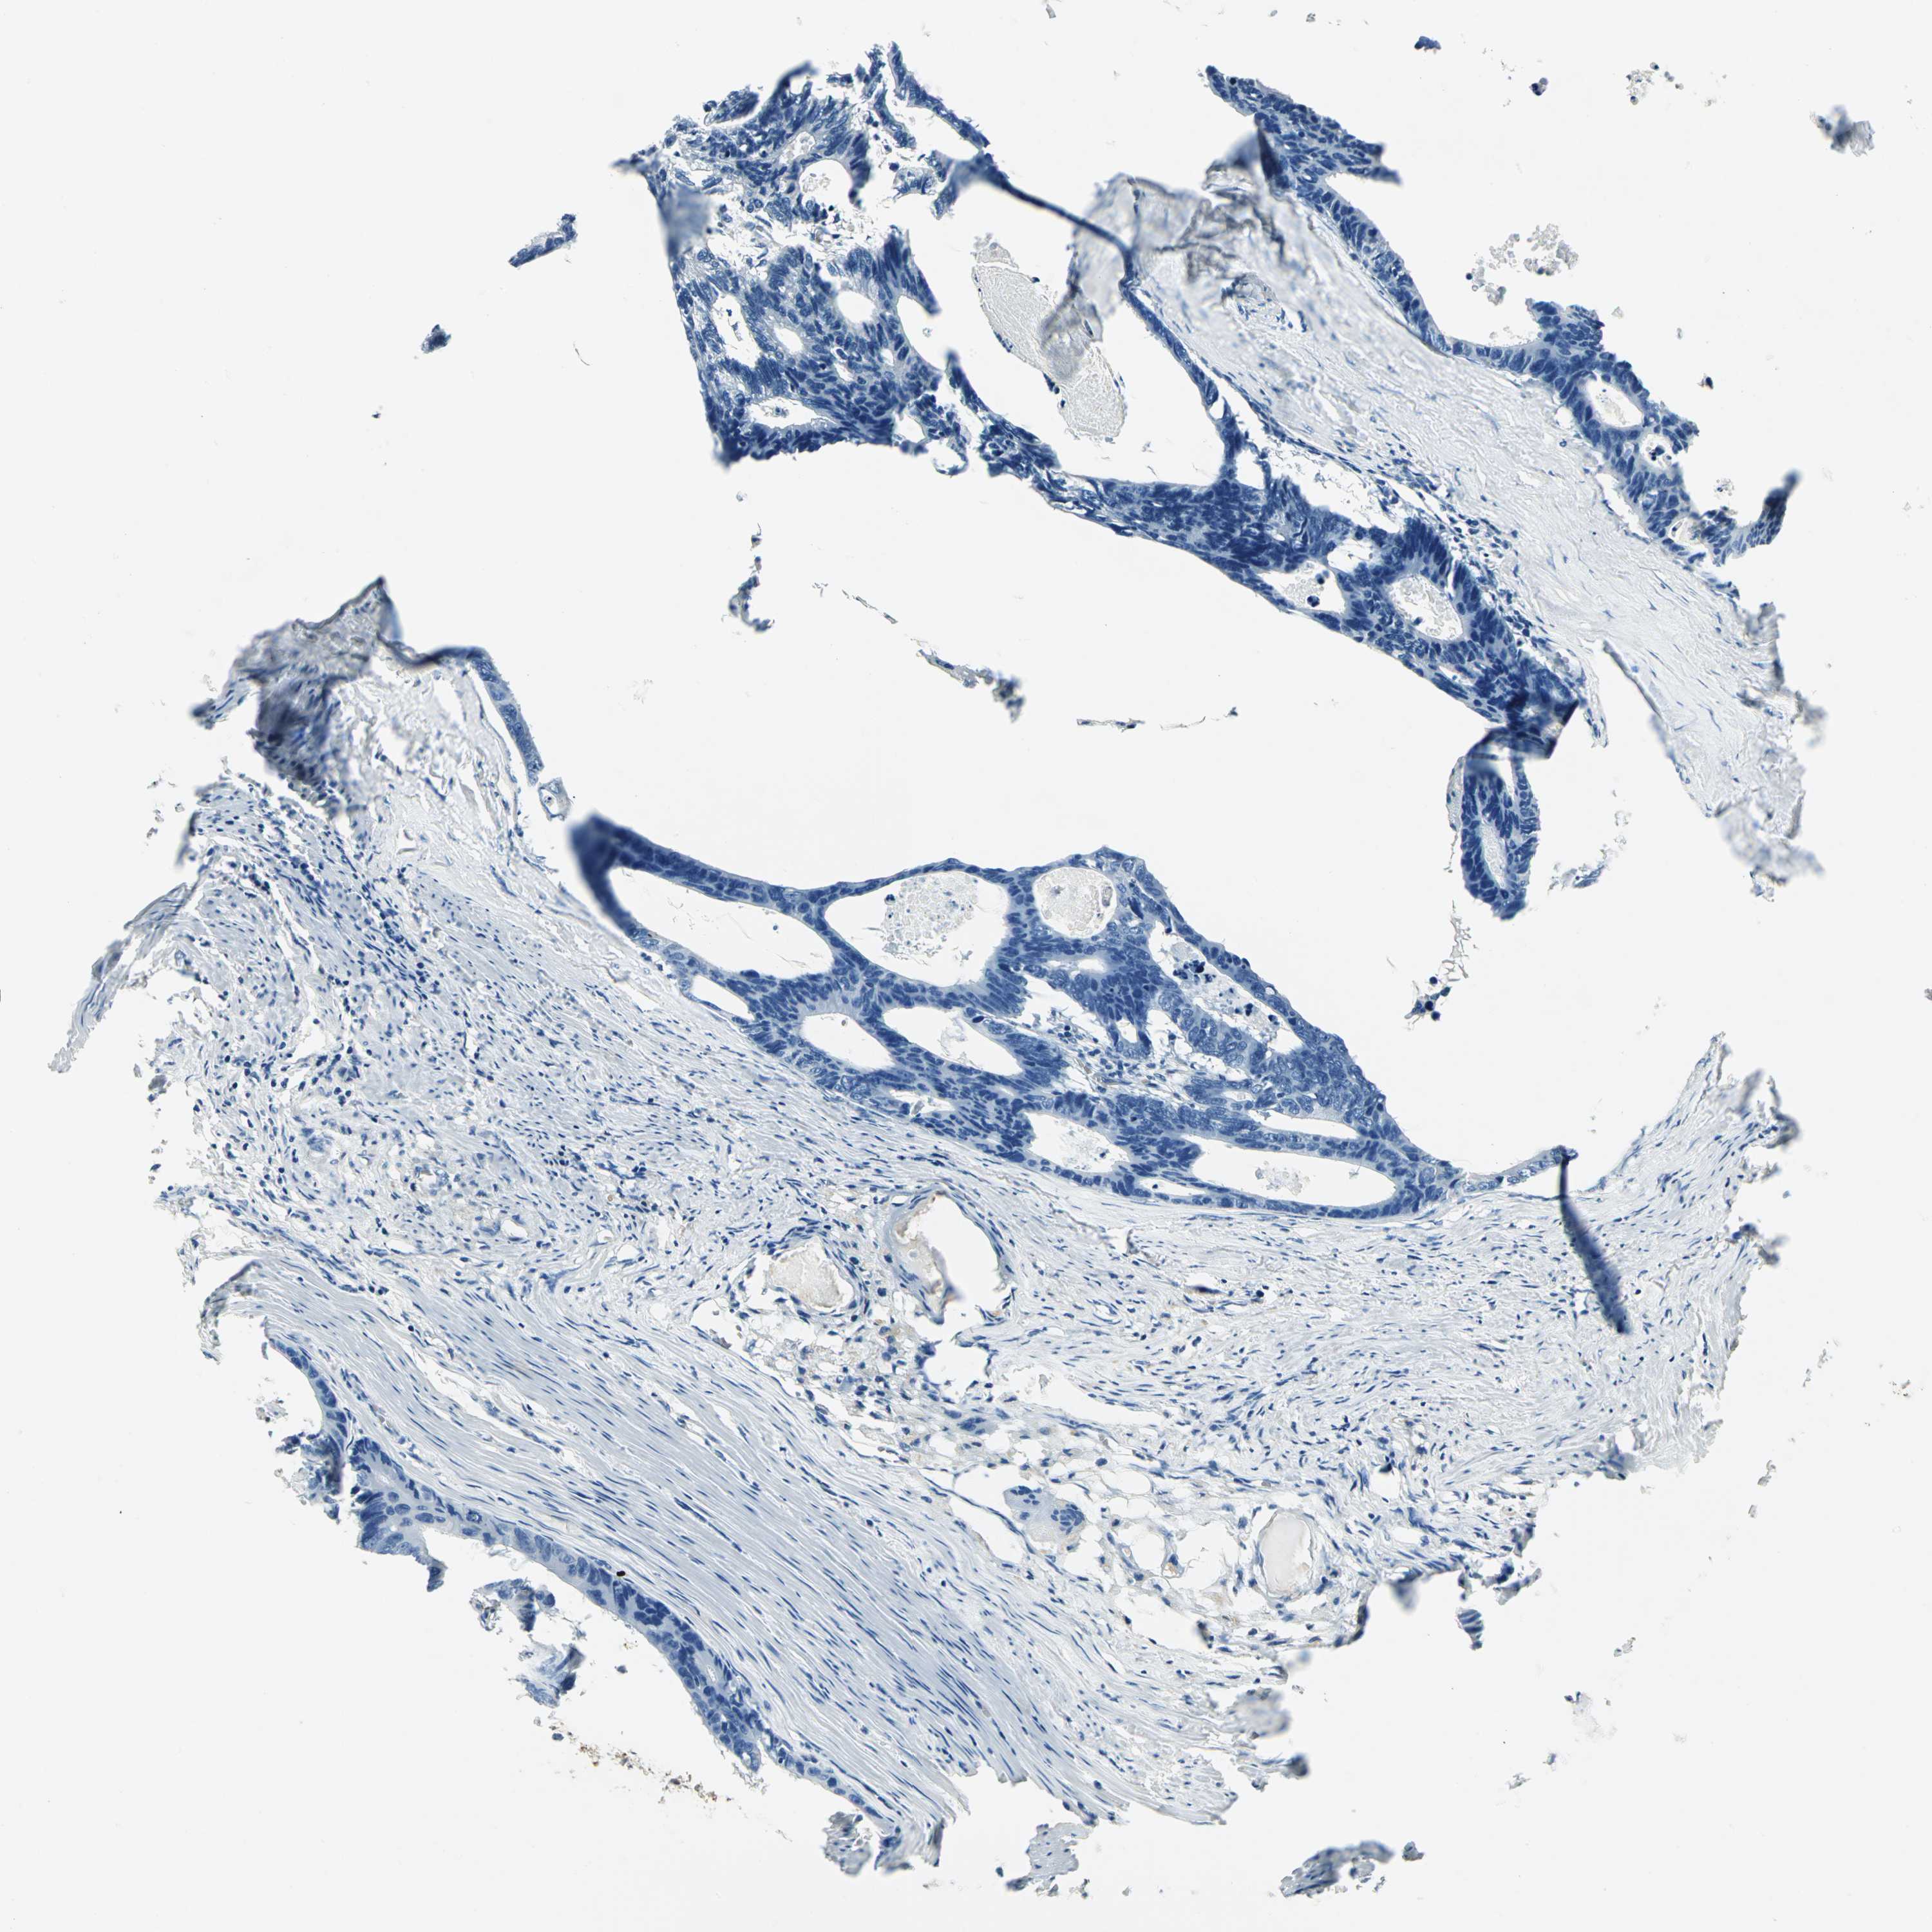

CANCER COLORECTAL CANCER Show tissue menu

COAD TCGA COAD VALIDATION READ TCGA READ VALIDATION PROTEIN COAD CPTAC PROTEIN EXPRESSION

ANTIBODIES

AND

VALIDATION